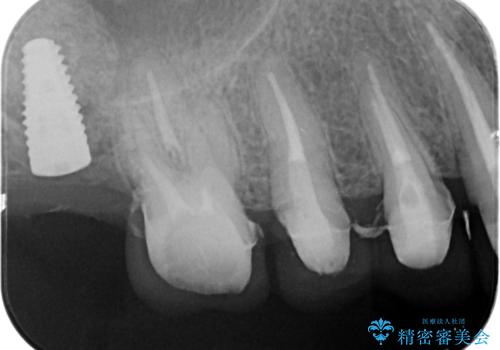

- 色や形、適合の悪いクラウンの再治療を希望され来院されました。

装着されているクラウンを除去し、自然な色調のジルコニアクラウンによる審美生の改善、インプラントを用いた欠損部の機能回復を計画します。

- 88万円(インプラント・チタンカスタムアバットメント・ジルコニアクラウン×4・仮歯×4)費用は治療当時の料金となります